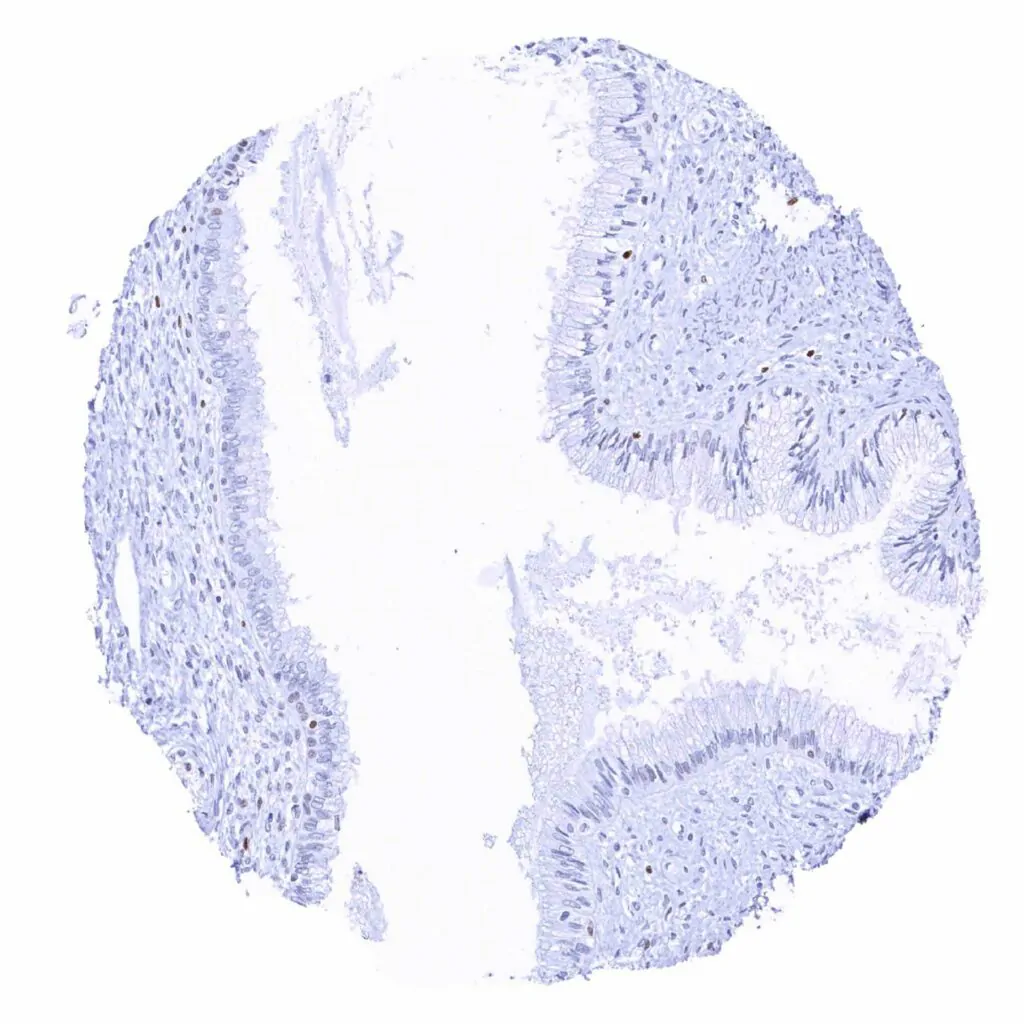

Uterus, endocervix – Only few epithelial cells show MCM2 staining